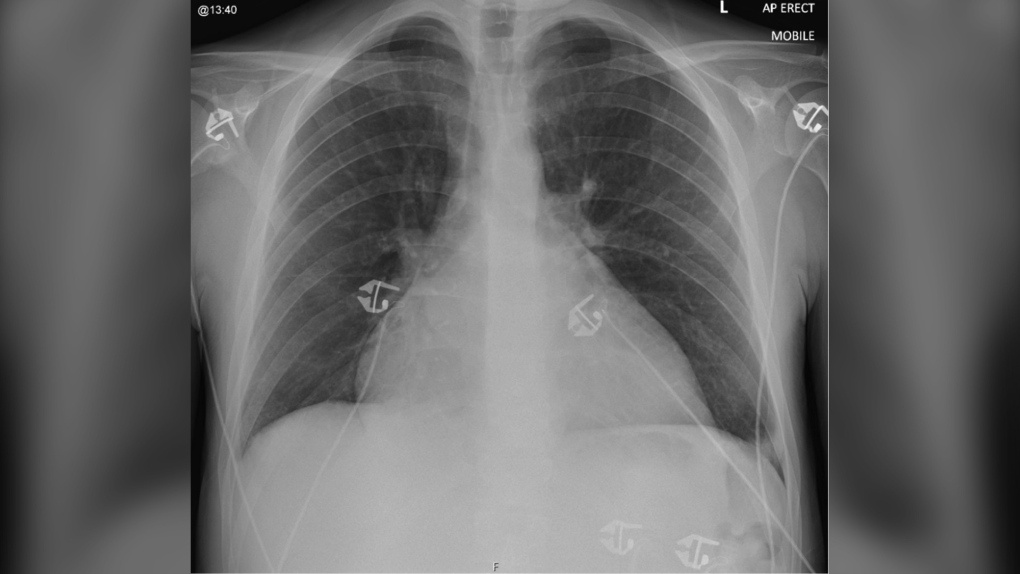

Hình chụp X-quang ngực khi nhập viện của bệnh nhân cho thấy tim có kích thước lớn bất thường. Ảnh: BMJ Case Reports.

Ghi chép từ nghiên cứu cho thấy ê-kíp chuyên gia phát hiện bệnh nhân bị suy tim, gây cản trở cho khả năng bơm, nhận máu. Trong đầu gối, ổ bụng của người này cũng bị tích đầy chất lỏng. Kết quả chụp X-quang cho thấy tim, phổi, gan của bệnh nhân giãn to. Bệnh nhân buộc phải nhập viện ngay và nằm trong phòng chăm sóc đặc biệt liên tục 58 ngày.